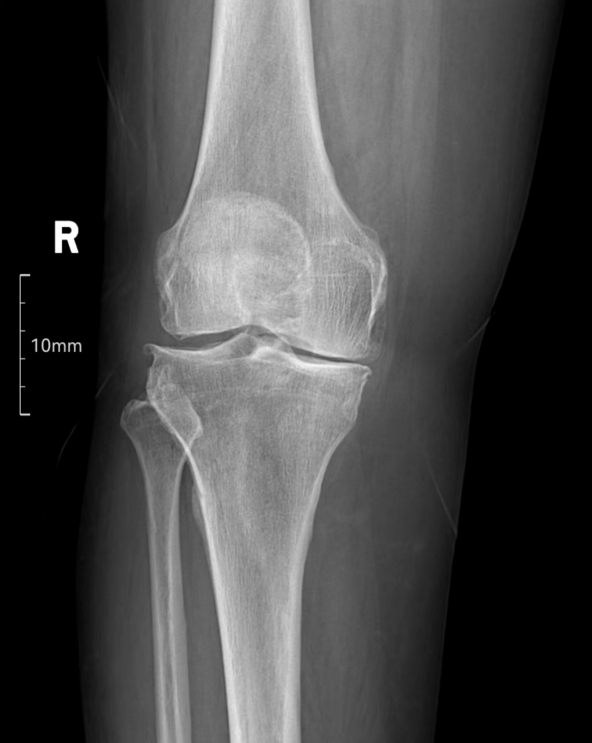

(术前X线)入院后,贵州医科大学第三附属医院骨科副主任、副主任医师王栋为崔奶奶进行了详细查体和检查,发现崔奶奶右膝关节明显内翻畸形,外侧软骨和半月板功能正常,比较适合行右侧胫骨近端高位截骨术。在与崔奶奶及家属沟通后,决定实施该手术,为她保住膝盖。 术前,贵医附院骨科主任医师、博士后叶川与贵州医科大学第三附属医院骨科团队一起,展开了科学而全面地评估及讨论,借助计算机软件,围绕切口、暴露部位、股骨截骨线和截骨量等,制定了详细精确的术前规划。手术当天,过程十分顺利,创伤较小,出血量少。术后,崔奶奶恢复了右下肢正常的生物力线。通过手术,她的右膝畸形不仅得到了矫正,而且膝关节的稳定性和活动度也得到了最大程度的保留。右膝屈伸活动基本不受限制,疼痛也明显缓解,崔奶奶及家属都很满意。术后情况